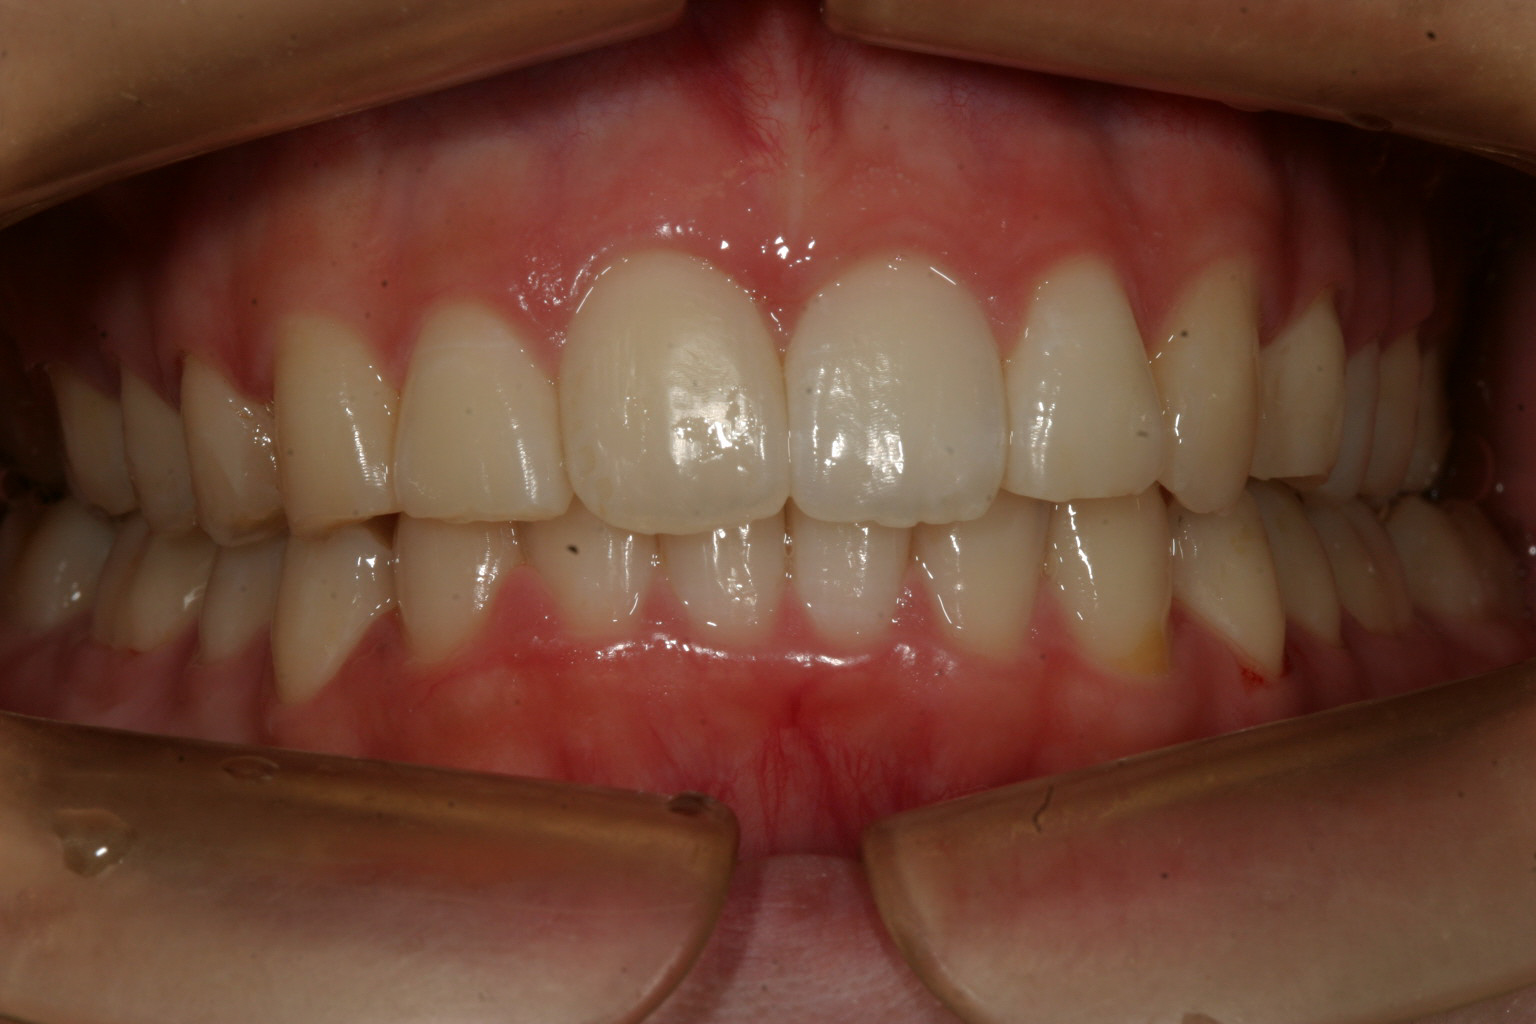

綺麗なアーチにしました。

下顎も綺麗なアーチにしないと噛めませんからね!

飛び出しも無くなりました。